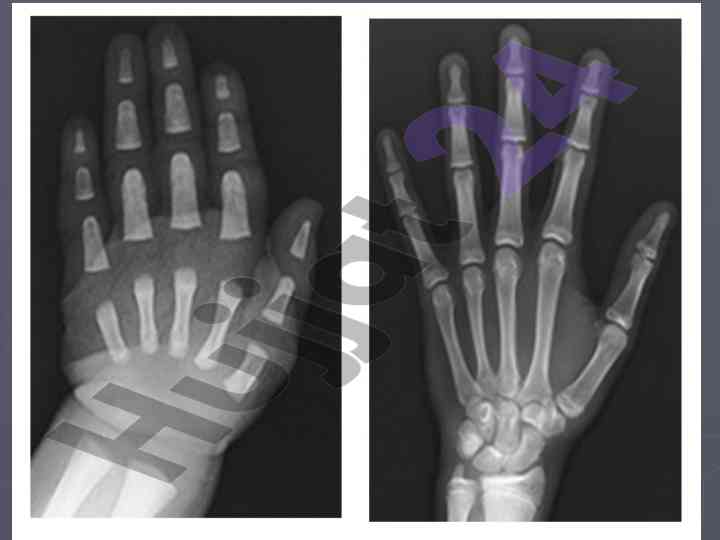

Bolalarda suyak tizimining xususiyatlari va siniqlar

Bolalarda suyak tizimining xususiyatlari, suyaklarni sanchish turlari va regeneratsiya jarayonlari, diagnostika va usish zonalari haqida ma'lumot.